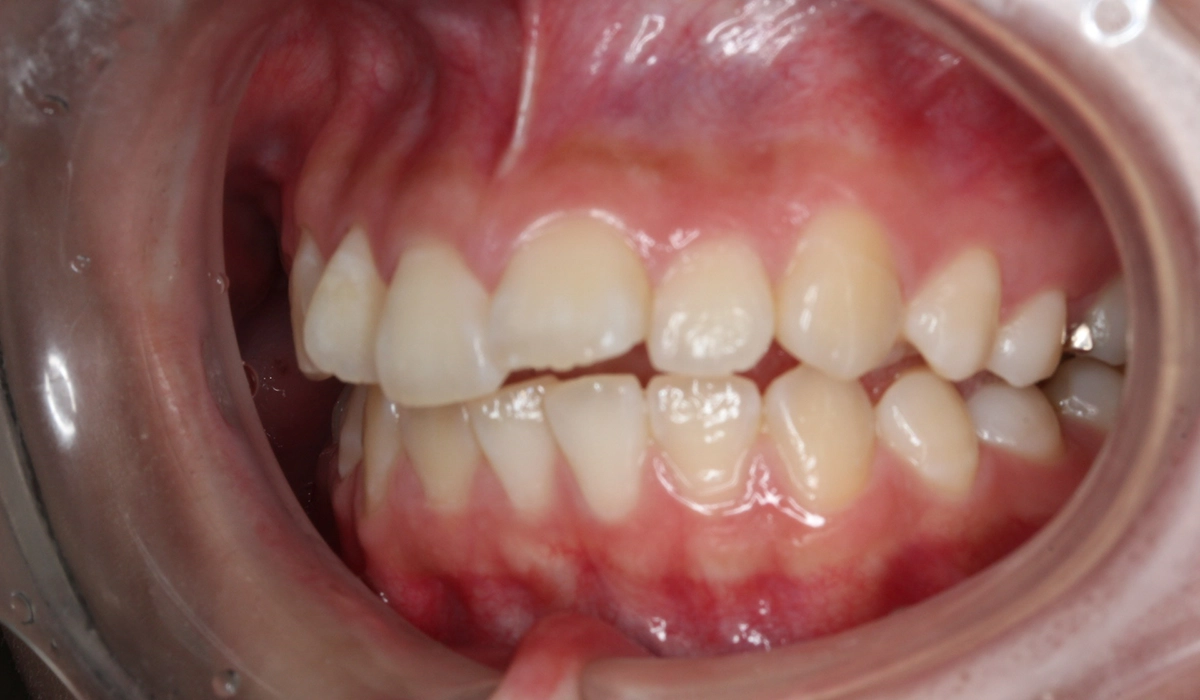

術前:右側

術後:右側